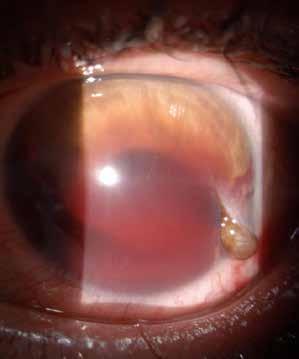

Type 2 MNV refers to the proliferation of new vessels originating from the choroid into the subretinal space. These vessels penetrate through the sub-RPE, making the subretinal portion the dominant component of the pathological process in Type 2 neovascularization. On FA, these lesions are usually “well-defined” as they present a well-demarcated area of hyperfluorescence in the early phase of the angiogram, followed by progressive dye pooling in the overlying subsensory retinal space during the late phase. (Figure 2)

Figure 2. Multimodal imaging of Type 2 macular neovascularization. Infrared reflectance (A) and fundus autofluorescence (B) revealing abnormalities of retinal pigment epithelium. Early and late phase of indocyanine green angiography (C and D) and fluorescein angiography (E and F) showing a well-defined neovascular network. Optical coherence tomography angiography (G) displaying the neovascular network. Optical coherence tomography (H) showing the neovascularization above the retinal pigment epithelium with disorganization of the overlying inner segment/outer segment junction.